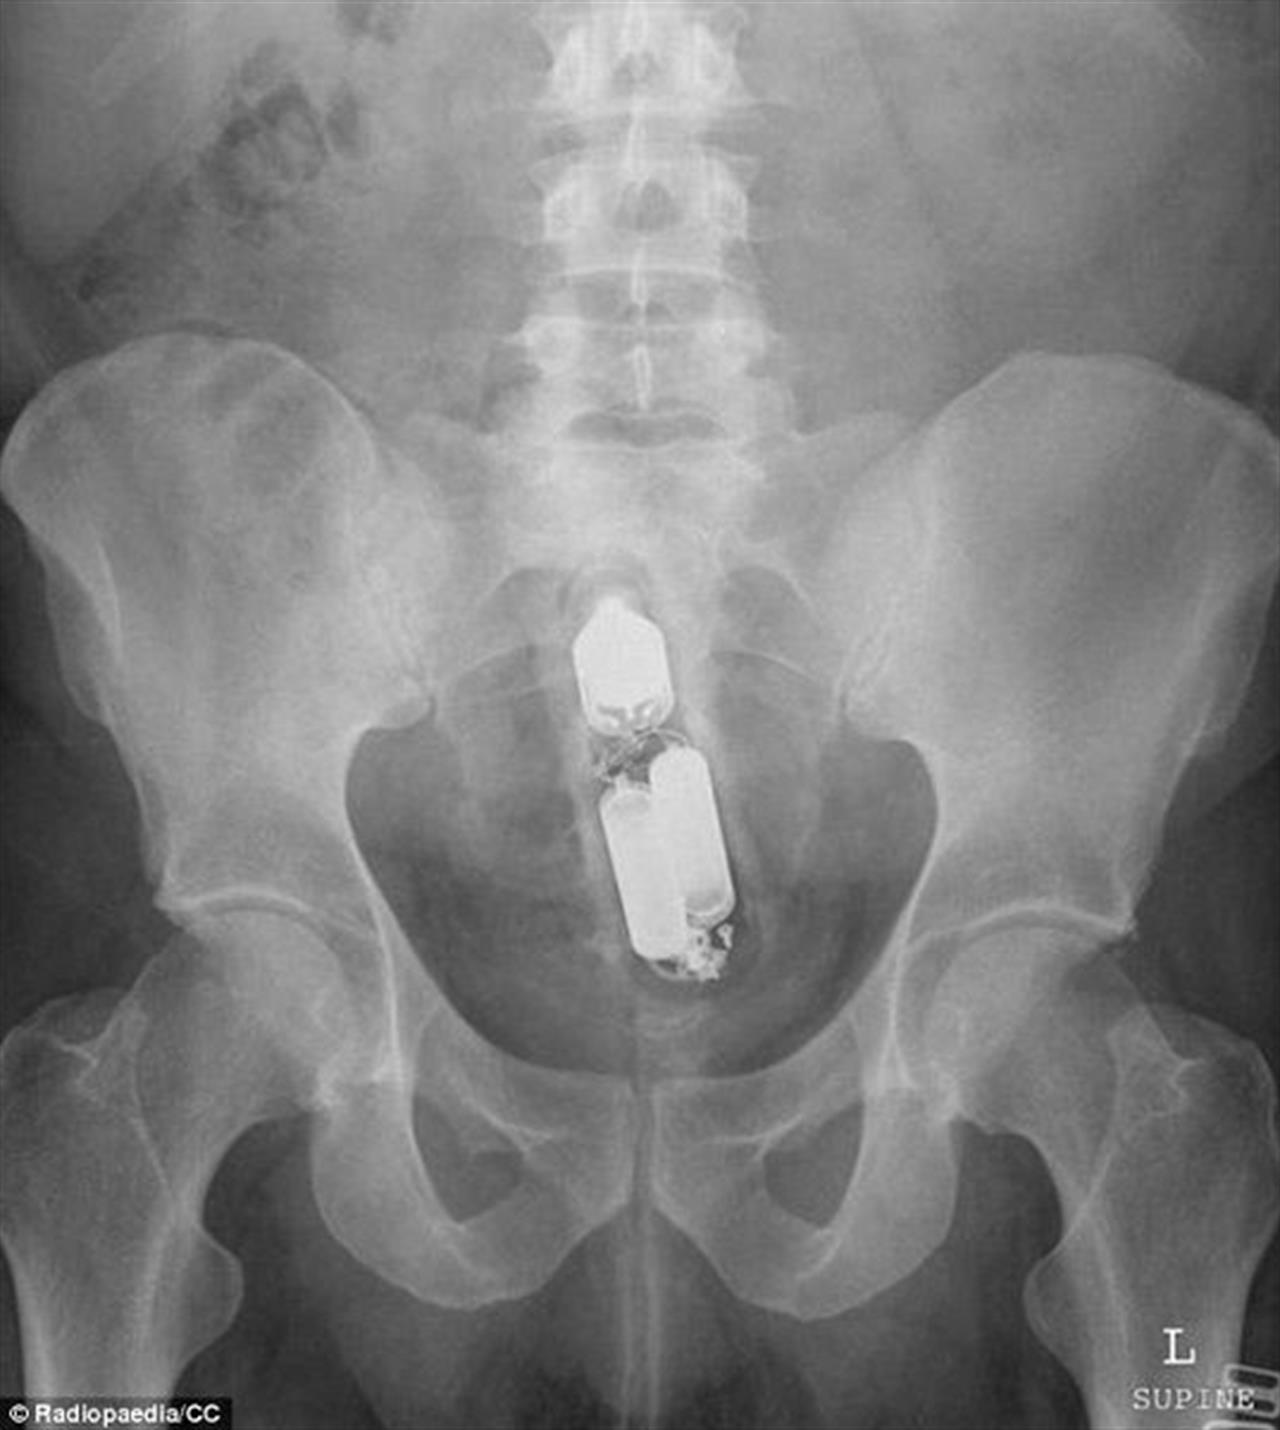

▼也曾有醫生在患者的直腸內取出完整的瓶子!